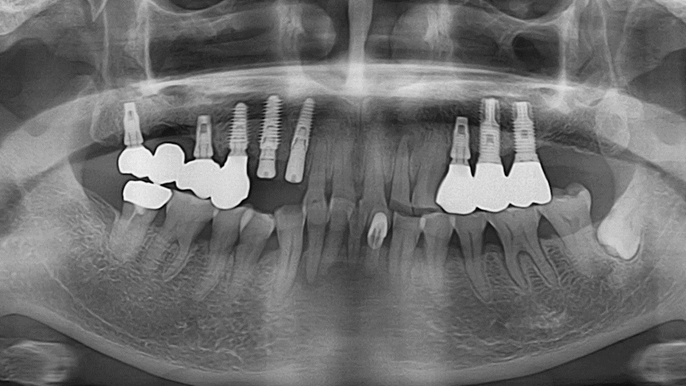

Dr. Sang Tack Lee, edentulous, digital full mouth prosthetics, digital guided surgery, #11, #13, #14, #16, #17, #21, #23, #24, #26, #27, #33, #34, #36, #37, #43, #44, #46, #47, guided surgery, flapless, AnyRidge, R2GATE, Mega ISQ, MEG Torq, MEG Engine, R2GATE Full surgical kit

AnyRidge implant system, R2GATE Guide, R2GATE full surgical kit , Mega ISQ